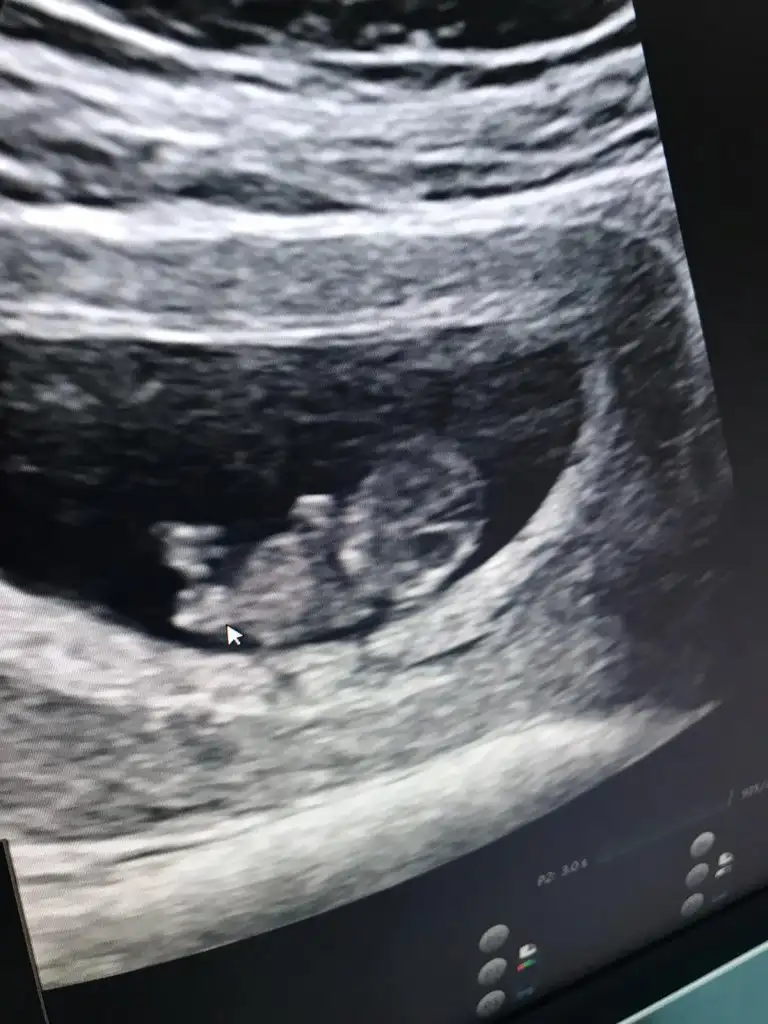

Yok karından baktı 9+2 ultrason görüntüsü bu 9+3 deyiz bugün. Bu 4. Gebeliğim ilk üçünde hiç kalp atışı bile yoktuk şimdi böyle bebek görüntüsü inanılmaz mutlu etti bizi inşallah tamamına erdirir.

Gayet iyi gidiyor iki gündür hafif kahverengi kanama var sorun değil dedi dr artık elleri ayakları bile oluşmuş 😊 oynatıyordu ultrasonda